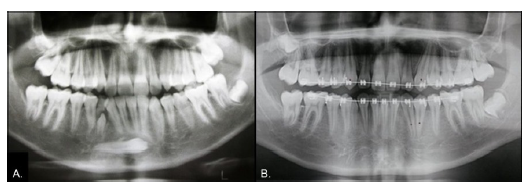

Case 4

Male, 25 years of age. Both the 2.3 and 4.3 were absent, with corresponding gaps, and the 2.2 was microdontic (Fig. 7). The radiograph showed that both missing teeth were in transmigration (Fig. 8A) and the inferior one was a type 2 transmigration. The patient decided on monitoring for both teeth to allow orthodontic treatment to open the spaces and then restore the errant canines to their places. The 2.5-year follow-up panoramic x-ray showed no significant changes (Fig. 8B).